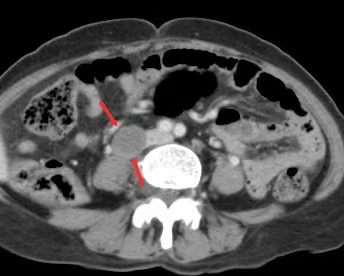

手术远比预想的要困难,术中发现,王女士的盆腔包块较大且伴有盆腔粘连,这大大增加了手术的难度和风险,而腹主动脉旁两枚2.5cm左右的增大淋巴结紧贴人体最重要及最粗血管之一的腹主动脉,分离过程犹如在刀尖上跳舞,必须十分谨慎,一旦动脉破裂,大出血、致命的危险将瞬间降临。任主任团队临危不惧,沉着冷静,凭借着丰富的经验、精湛的技术和顽强的毅力,顶住了巨大的压力和风险,在手术中小心细致地分离出转移增大的腹主动脉旁淋巴结,经过5个小时的紧张奋战,成功地完成了这一高难度的手术操作。